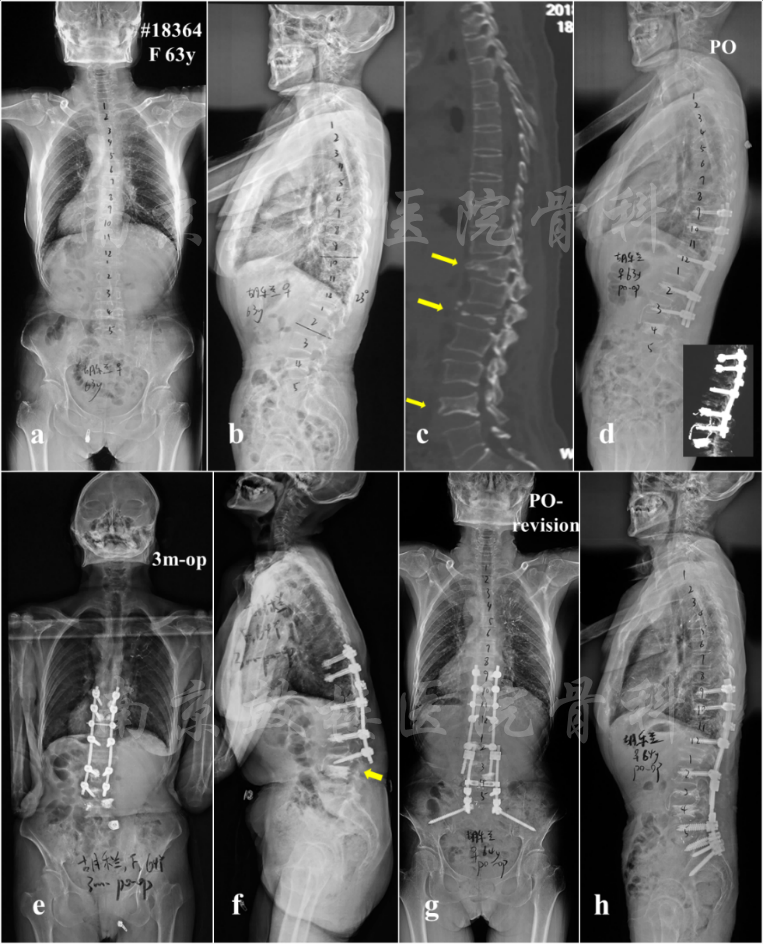

出现远端内固定失败的危险因素主要包括高龄、肥胖、骨质疏松等。患者术前存在较大的骨盆入射角或严重的矢状面失平衡,术后腰椎前凸及矢状面平衡重建不良也是其发生的危险因素。此外,手术时内固定植入不牢固、骨质疏松(图2)、机械负荷过大、融合区域不稳导致内固定机械应力过大、以及外伤或术后从事体力劳动等也是腰骶部内固定失败的原因。

图2 女,63岁,多发骨质疏松性骨折(T11,L1,L4),类风关病史,长期服用激素(b, c);初次手术行骨折切开复位内固定(T9-L3),其中T9,T10,L2及L3均使用骨水泥螺钉加强,L4椎体行骨水泥注入(d);术后3个月出现远端交界性失败(DJK),L3螺钉拔出,矢状面躯干失平衡(e, f);行翻修术,将内固定延长至骨盆并使用S2AI螺钉固定,L4/5及L5/S1行TLIF支撑(g, h)